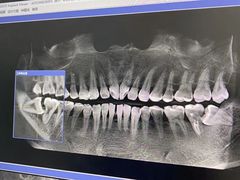

• 美冠塔口腔(酒仙桥分院)

• -美冠塔口腔(酒仙桥分院)